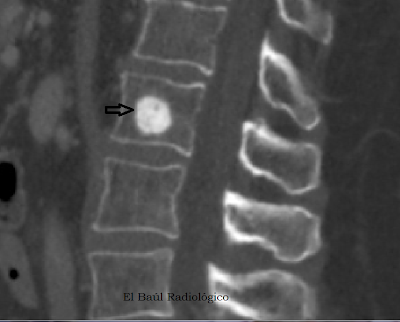

FIGURA 3) En esta imagen de TC lumbar con resconstrución multiplanar, MPR, la lesión aparece como una formación ósea densa. Parece una lesión benigna: bien delimitada, poco agresiva y compacta.

(In this lumbar CT imaging with multiplanar reconstruction, MPR, the lesion appears as a dense bone formation. It seems a benign lesion: well defined, not very aggressive and compact).